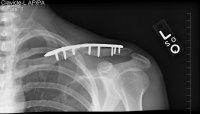

Xrays

Update: August 23, 2010

Saw the Doc again, he's pleased with the results, but it's just going to take more time. If you look at the x-rays you can see that the void is closing, slowly.

He seemed very confidant that it should be ok by T-Day, will know more in 6 weeks.